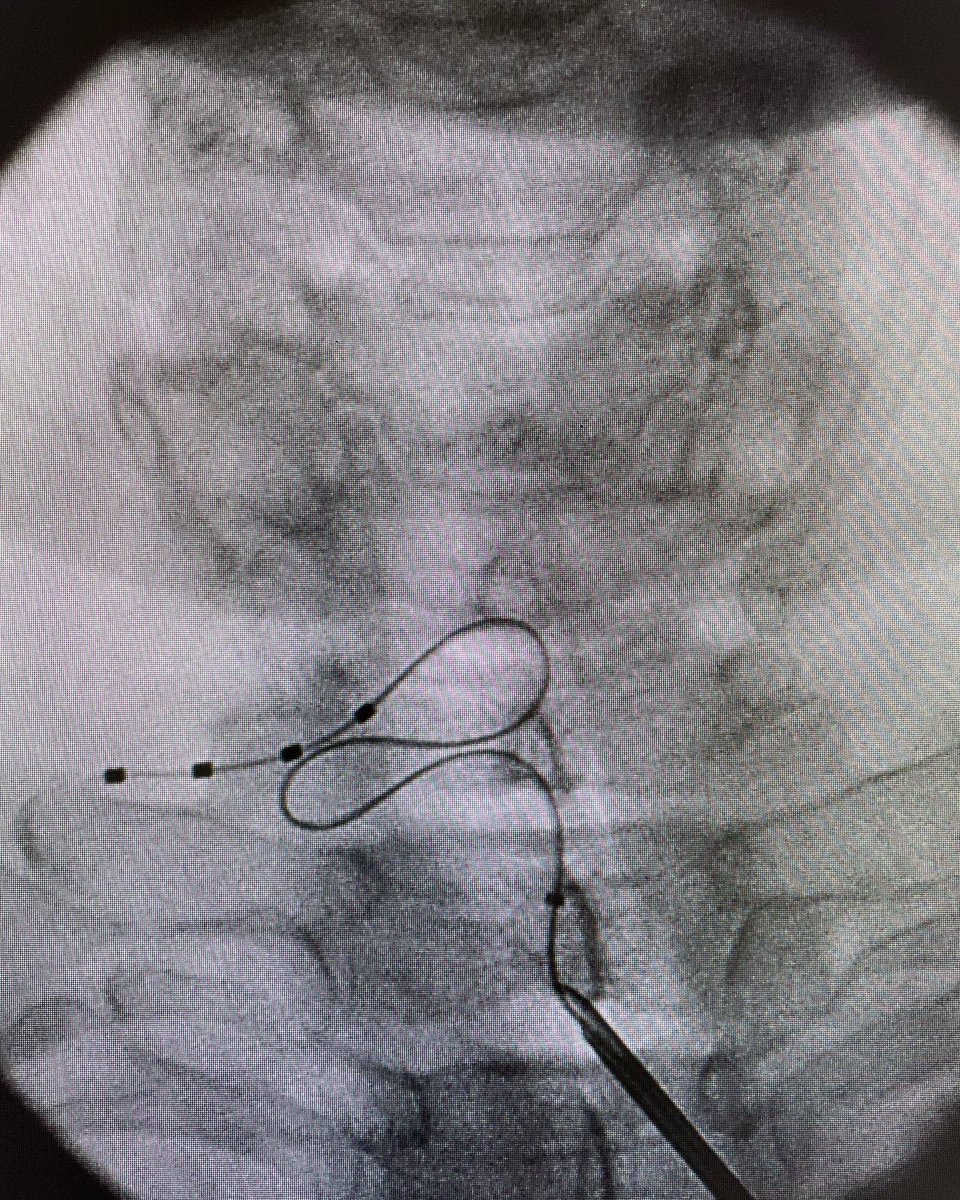

DRG cervical para el tratamiento de SDRC localizado en la mano junto la Dra. Luz Canovas, a una de las personas que más ha aportado al tratamiento del dolor en España.